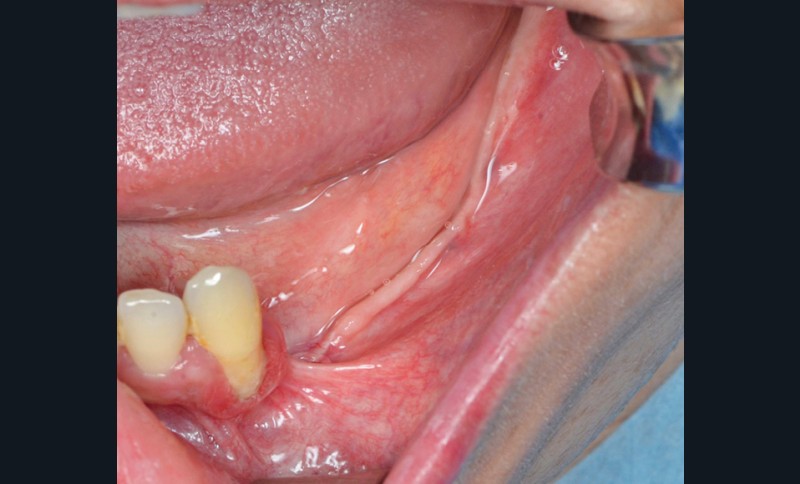

L’edentement est important de 33 à 38 et implique un prélèvement de grande étendue (fig. 2).